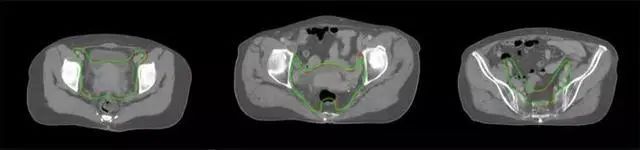

放射治療,簡稱放療,是治療腫瘤主要手段之一,利用放射線破壞照射區(qū)(靶區(qū))的細(xì)胞,使腫瘤細(xì)胞停止分裂直至死亡,醫(yī)生通常把放射治療形象的比喻為“打靶”,放療前精準(zhǔn)勾畫腫瘤靶區(qū)范圍是腫瘤放射治療的關(guān)鍵步驟。傳統(tǒng)的靶區(qū)勾畫醫(yī)生會根據(jù)患者多張CT、MRI影像片憑借經(jīng)驗(yàn)進(jìn)行,比較耗時,治療的病人數(shù)量也有限,且靶區(qū)勾畫缺少行業(yè)統(tǒng)一的規(guī)范和標(biāo)準(zhǔn),無法達(dá)到同質(zhì)化,勾畫精確度不理想。

技術(shù)原理

基于深度學(xué)習(xí)人工智能的放療靶區(qū)智能勾畫技術(shù)和自動計(jì)劃技術(shù),基于全面的市場調(diào)研和臨床專業(yè)意見,采用獨(dú)創(chuàng)的基于小樣本量的人工智能算法,實(shí)現(xiàn)放療靶區(qū)和危及器官的快速全自動勾畫。

產(chǎn)品優(yōu)勢

縮短至幾分鐘內(nèi)便可完成,大幅提升了放療效率,且人工智能平臺完成的靶區(qū)勾畫可基本滿足臨床醫(yī)生需求,專家只需審核時細(xì)微調(diào)整,可顯著提高靶區(qū)勾畫的規(guī)范化及精準(zhǔn)度,讓放療智能化,標(biāo)準(zhǔn)化。可覆蓋食管癌、鼻咽癌、直腸癌、宮頸癌、肺癌等多種病種。